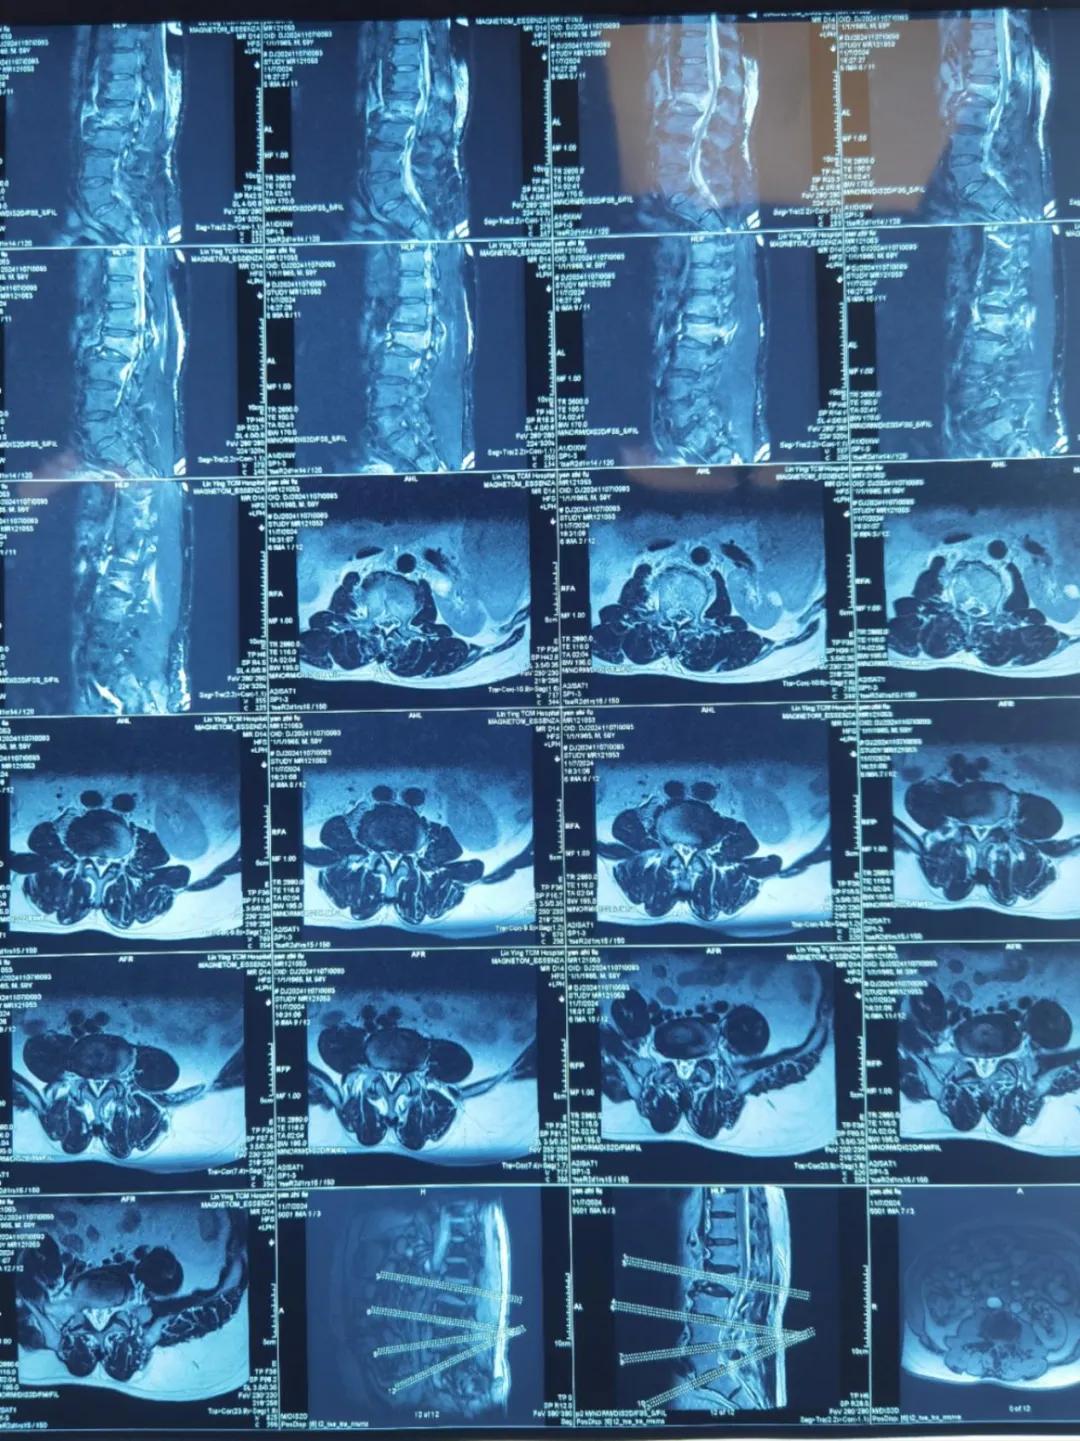

“醫(yī)生,這是之前的檢查結果,還需要再做檢查嗎?”閆大叔從外院轉來被推進智能微創(chuàng)骨科。幾天前,他在老家的中醫(yī)院進行了抽血檢驗和磁共振檢查,因為腰疼嚴重、行動不便檢查過程也十分不易。

智能微創(chuàng)骨科副主任李鵬認真檢查了閆大叔帶來的片子,還有電腦系統(tǒng)上彈出來的檢驗結果。外院的核磁和X線可以清楚的看到情況已經比較嚴重,需要盡快手術。沒有二次檢查,不僅節(jié)省患者就醫(yī)費用,還使就醫(yī)更高效、便捷直接入院接受治療。閆大叔懸著的心放了下來,其他醫(yī)院的片子能直接用,檢查在家附近的醫(yī)院做,手術在漯河市骨科醫(yī)院做,便捷的結果'互認'讓他直夸“真方便!咱老百姓更省心、更放心了!”